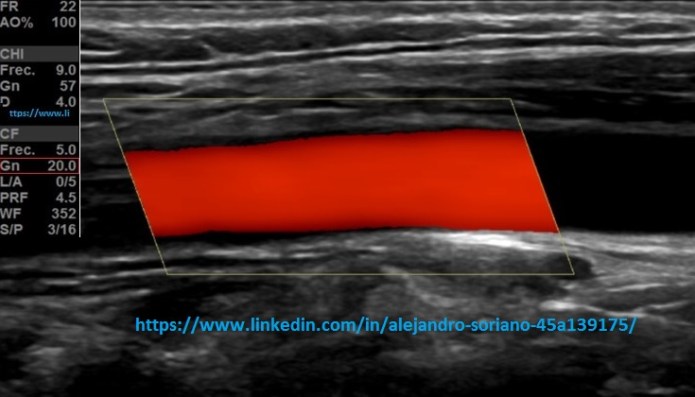

- Ganancia: sabremos que tenemos la ganancia adecuada cuando no veamos artefacto en “confeti” que se produce por exceso de ésta; y cuando veamos el vaso relleno por completo ya que veremos zonas sin pintar cuando la ganancia es baja.

- Tendremos en el mismo botón del modo de trabajo del Doppler, la capacidad de variar este valor, girando la rueda.Esto es de modo general, puede haber excepciones, según cada casa comercial.

Gain: we will know that we have the adequate profit when we do not see an artifact in «confetti» that is produced by excess of it; and when we see the filled glass completely since we will see unpainted areas when the gain is low. We will have in the same button Doppler work mode, the ability to vary this value, turning the wheel. This is generally, there may be exceptions, according to each commercial house.